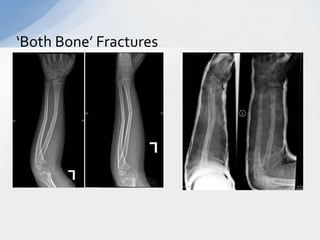

‘Both Bone’ Fractures

• Both bone